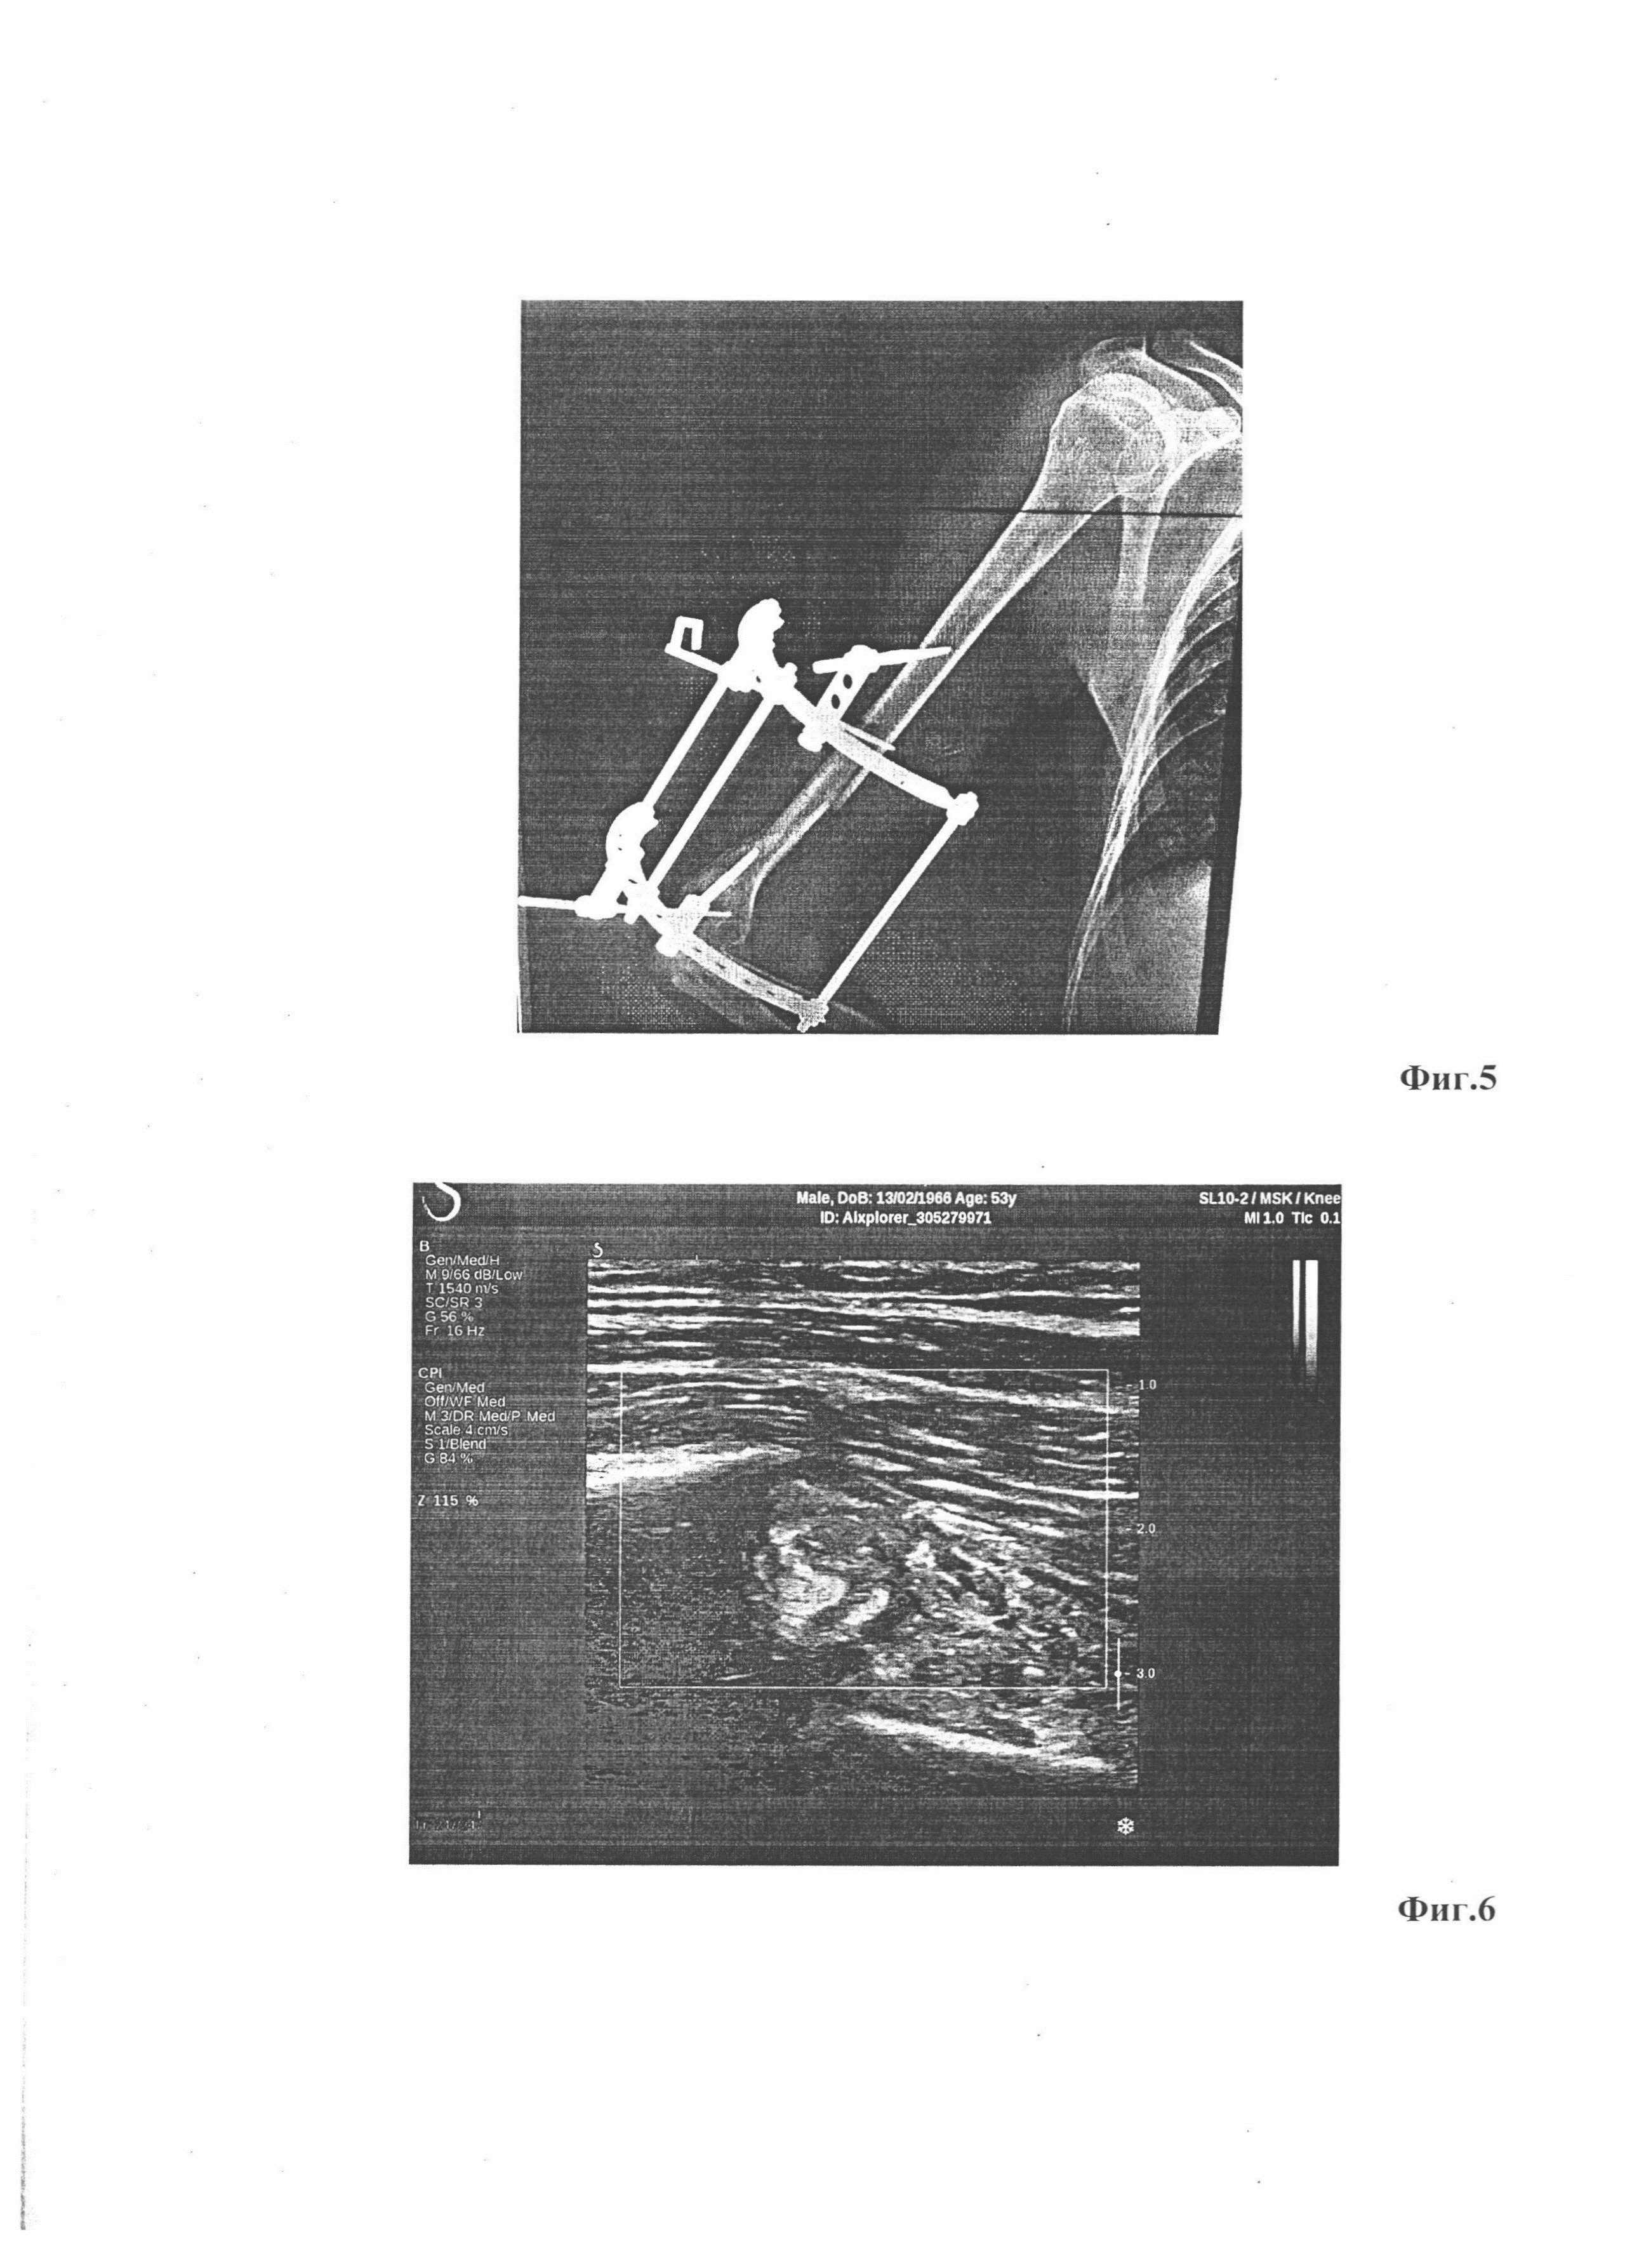

[26]

На фиг. 5 - Рентгенограмма пациента М. Закрытый винтообразный перелом нижней трети правой плечевой кости со смещением. Проведена операция: фиксация костных отломков металлической конструкцией.

[39]

Пациент М., 1966 г.р., доставлен в травматологическое отделение ГАУЗ «РКБ МЗ РТ» машиной скорой помощи, с жалобами на боли в нижней трети правой плечевой кости. После обследования поставлен диагноз: закрытый винтообразный перелом нижней трети правой плечевой кости со смещением. Проведена операция: фиксация костных отломков аппаратом внешней фиксации (фиг. 5). На 7-й день после операции, для контроля зоны перелома, исследования окружающих мягких тканей и сосудов, и исключения интерпозиции мышечными тканями, пациент направлен на УЗИ.